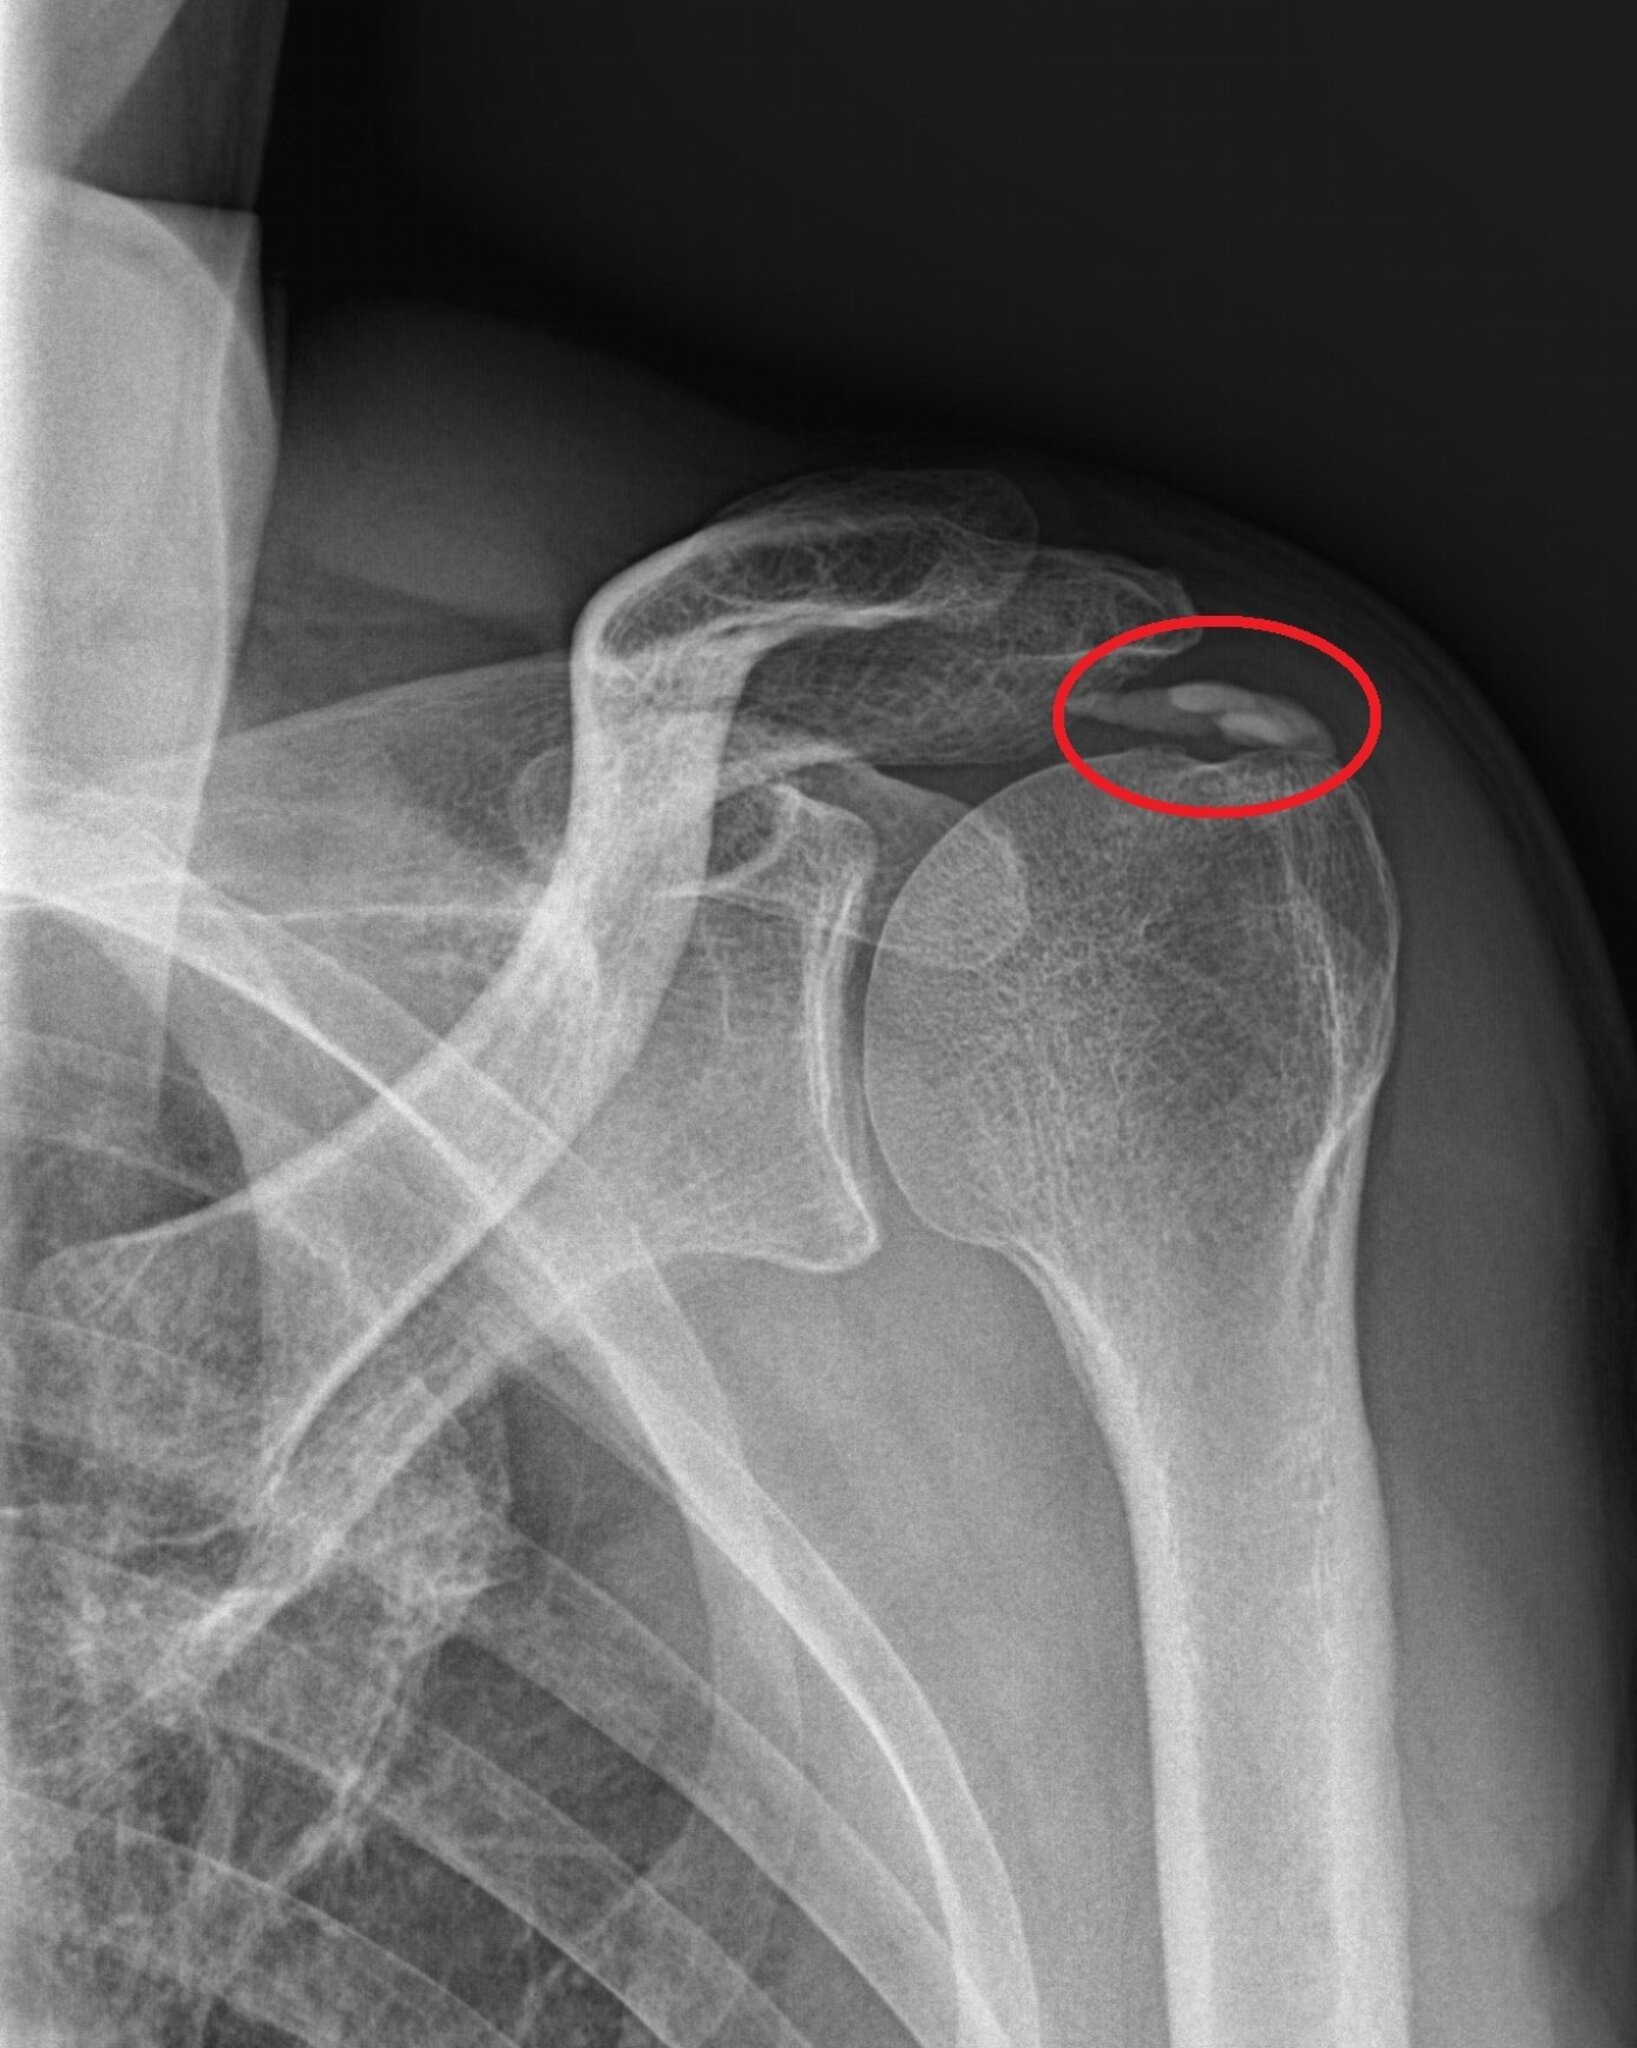

KALKSCHULTER Beschreibung Bei dieser Erkrankung bilden sich kalkartige Ablagerungen in den Sehnen und Schleimbeuteln der Schulter. Die Ursache für diese als Kalkschulter bezeichnete Erkrankung ist noch nicht genau geklärt. Die Kalkschulter (Tendinitis calcarea) bezeichnet eine schmerzhafte, entzündliche Erkrankung der Schulter, die durch Kalkablagerungen in den Sehnen der Rotatorenmanschette zustande kommt. Am häufigsten von diesen Kalkablagerungen betroffen ist die Ansatzsehne des Musculus supraspinatus (Supraspinatussehne). Übersicht Bei einer Kalkschulter – auch Tendinosis calcarea genannt – kommt es zu einer Einlagerung von Kalk in eine Sehne des Schultergelenks. Am häufigsten ist die Supraspinatussehne betroffen. Ein Kalkdepot kann wenig Probleme

Die Kalkschulter ist eine Erkrankung mit Kalkablagerungen in den Sehnen der Rotatorenmanschette und tritt meist ohne erkennbaren Auslöser auf. Es kommt häufig zur Verdickung der Sehne unter dem Schulterdach, dadurch können Beschwerden wie beim Engpass-Syndrom ausgelöst werden. Die Kalkschulter oder Tendinosis calcarea der Rotatorenmanschette hat sich heutzutage als eigenständiges Krankheitsbild herausgestellt. Therapieverfahren wie die arthroskopische Kalkdepotentfernung und die extrakorporale Stoßwellentherapie haben das Interesse in den vergangenen Jahren neu geweckt.

Die Kalkschulter verläuft oft beschwerdefrei, in vielen Fällen ist sie ein Zufallsbefund im Rahmen einer Röntgenuntersuchung. Oft klagen Patienten und Patientinnen über nächtliche Schmerzen: Ein Schlafen auf der betroffenen Schulter ist meist nicht mehr möglich.

Bei einer Kalkschulter (medizinischer Fachbegriff Tendinosis calcarea) kommt es zu einer Einlagerung von Kalk in die Sehnen der Rotatorenmanschette. Am häufigsten betroffen ist die Sehne des Musculus supraspinatus, die Supraspinatussehne. Sie verläuft zwischen Oberarmkopf und Schulterdach. Das Kalkdepot in der Sehne kann ohne Beschwerden bleiben